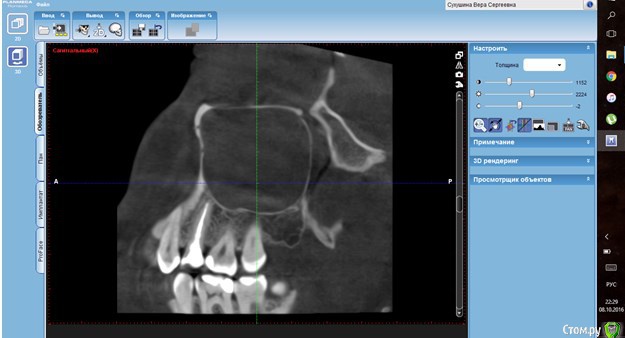

Verasss Опубликовано 8 октября, 2016 Автор Поделиться Опубликовано 8 октября, 2016 КТ от 08.09. Извините, что в таком виде, надо менять ОЗУ. Ссылка на комментарий

Verasss Опубликовано 28 октября, 2016 Автор Поделиться Опубликовано 28 октября, 2016 Добрый вечер! Ещё раз попытаюсь прикрепить скриншоты КТ от сентября. Если качество совсем не устраивает, подскажите, пожалуйста, какие сделать снимки?К сожалению, программа не позволяет вывести снимки на полный экран и заскриншотить в более хорошем качестве. Ссылка на комментарий